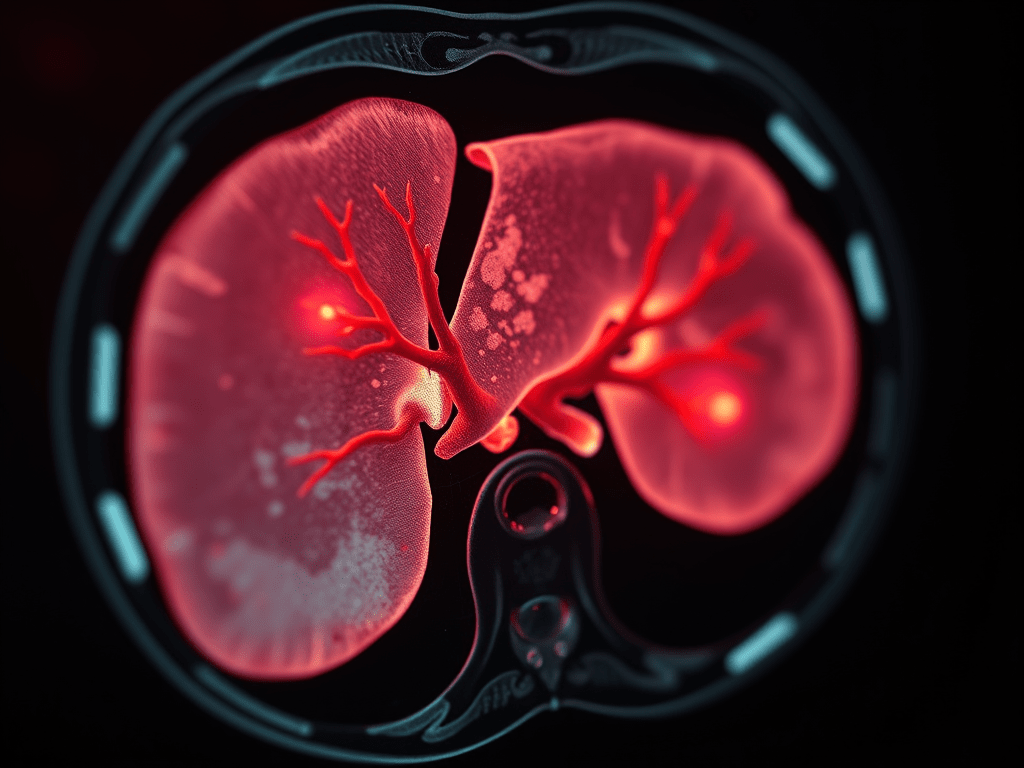

馬家榮醫生解釋肝血管瘤主要是指肝臟的海綿狀血管瘤(cavernous hemangioma),是肝臟內的海綿狀血管腔組織出現畸形的情況,屬於常見的肝臟良性病變,即是不屬於可出現細胞異常增生的癌症類別,也不會演變成肝癌。

他指出臨床上有小部份患者可能會因肝血管瘤較大(大至4至5厘米)而有擠壓感,惟不適感的嚴重程度卻大多取決於病灶位置,例如當血管瘤貼著肝臟外層的肝膜,由於肝膜佈滿神經缐,故易有脹痛或「扯住」、「頂住」等不適症狀。若不幸血管瘤生在肝臟較前近肚皮的位置,更會因易受「擠壓」而可致穿破或流血,患者會突然間感到劇痛,須即時送院醫治,因為若所流的血湧到腹膜,會引致肚脹或因嚴重失血而休克。